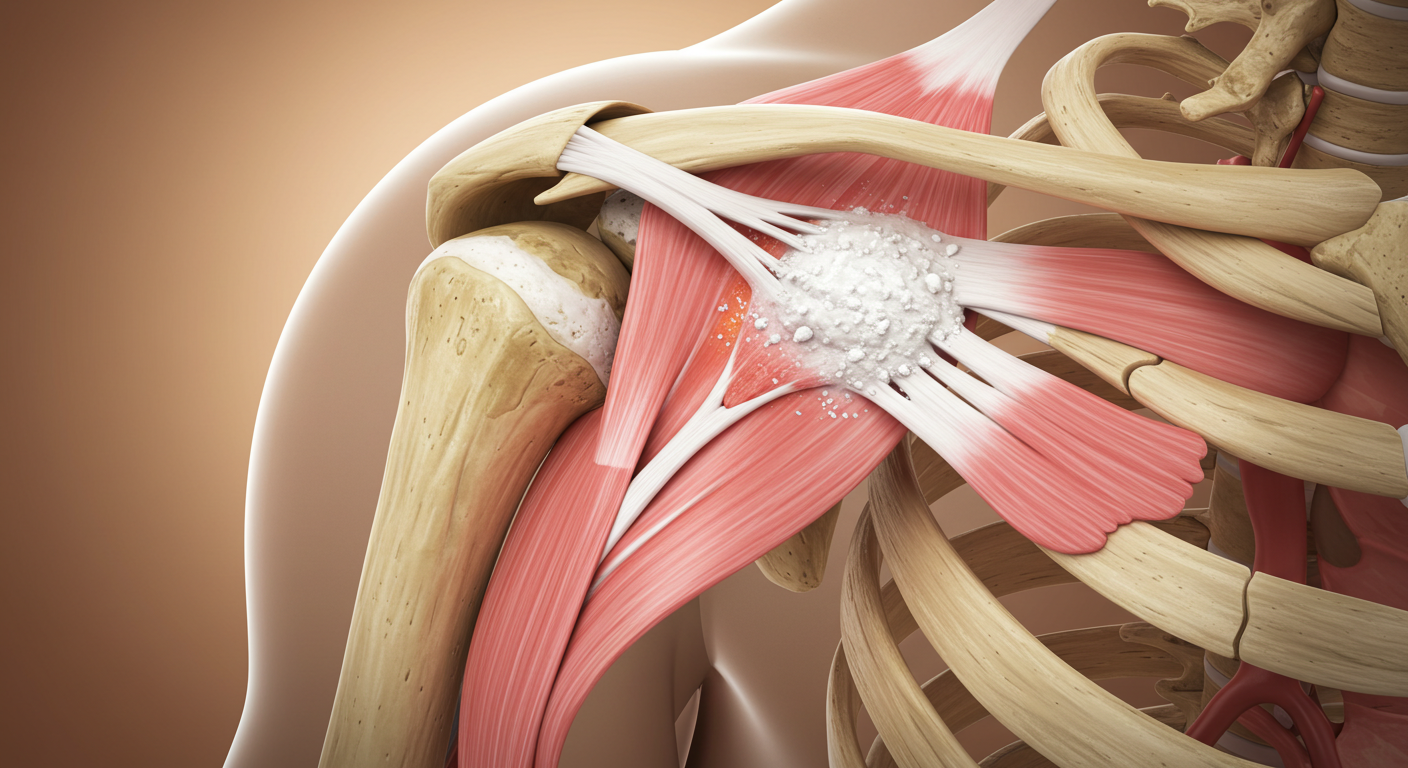

석회성 힘줄염은 말 그대로 어깨 힘줄에 석회(칼슘)가 침착되어 염증을 일으키는 질환이에요. 아직까지 정확한 원인은 밝혀지지 않았지만, 주로 힘줄의 퇴행성 변화나 미세한 손상, 혈류 감소 등이 원인으로 지목되고 있습니다. 30~50대 연령층에서 비교적 흔하게 나타나는데, 특히 어깨를 많이 사용하는 직업이나 반복적인 운동을 하는 분들에게 더 잘 생긴다고 해요. 꼭 나이가 많아야 생기는 건 아니라는 거죠.

- 퇴행성 변화: 나이가 들면서 힘줄이 약해지고 미세 손상이 반복되면서 발생할 수 있어요.

- 혈액순환 장애: 힘줄 부위의 혈액순환이 원활하지 않아 석회가 쌓일 가능성이 높아집니다.

- 반복적인 사용: 특정 동작을 반복적으로 하는 것도 힘줄에 부담을 줘서 원인이 될 수 있습니다.